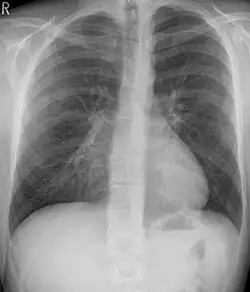

Pectus excavatum is initially suspected from visual examination of the anterior chest. Auscultation of the chest can reveal displaced heart beat and valve prolapse. There can be a heart murmur occurring during systole caused by proximity between the sternum and the pulmonary artery.[18] Lung sounds are usually clear yet diminished due to decreased base lung capacity.[19]

Many scales have been developed to determine the degree of deformity in the chest wall. Most of these are variants on the distance between the sternum and the spine. One such index is the Backer ratio which grades severity of deformity based on the ratio between the diameter of the vertebral body nearest to xiphosternal junction and the distance between the xiphosternal junction and the nearest vertebral body.[20] More recently the Haller index has been used based on CT scan measurements. An index over 3.25 is often defined as severe.[21] The Haller index is the ratio between the horizontal distance of the inside of the ribcage and the shortest distance between the vertebrae and sternum.[22]

Chest x-rays are also useful in the diagnosis. The chest x-ray in pectus excavatum can show an opacity in the right lung area that can be mistaken for an infiltrate (such as that seen with pneumonia).[23] Some studies also suggest that the Haller index can be calculated based on chest x-ray as opposed to CT scanning in individuals who have no limitation in their function.[24]